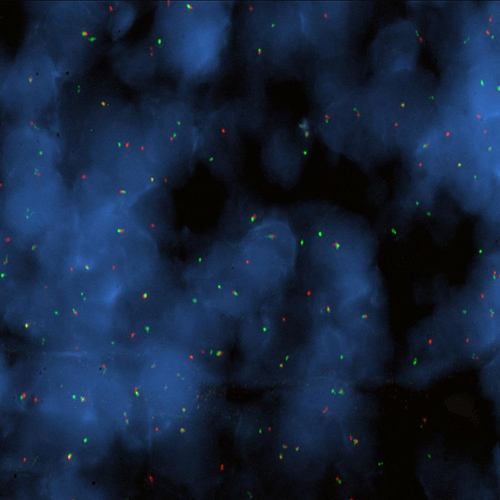

Hybridization of BCL6 break probe to a tissue section showing aberrant pattern (1RG1R1G).

Chromosomal translocations involving band 3q27 with various different partner chromosomes represent a recurrent cytogenetic abnormality in B-cell non-Hodgkin's lymphoma. Kreatech has developed this probe for the specific use on cell material (KBI-10607), or on tissue (KBI-10730). Two different breakpoint regions have been identified; the major breakpoint region (MBR) is located within the 5' noncoding region of the BCL6 proto-oncogene, while the atypical breakpoint region (ABR) is located approximately 200 kb distal to the BCL6 gene. The BCL6 (3q27) Break probe is designed to flank both possible breakpoints, thereby providing clear split signals. The BCL6 (3q27) Break probe is optimized to detect translocations involving the BCL6 gene region at 3q27 in a dual-color, split assay on paraffin-embedded tissue sections.